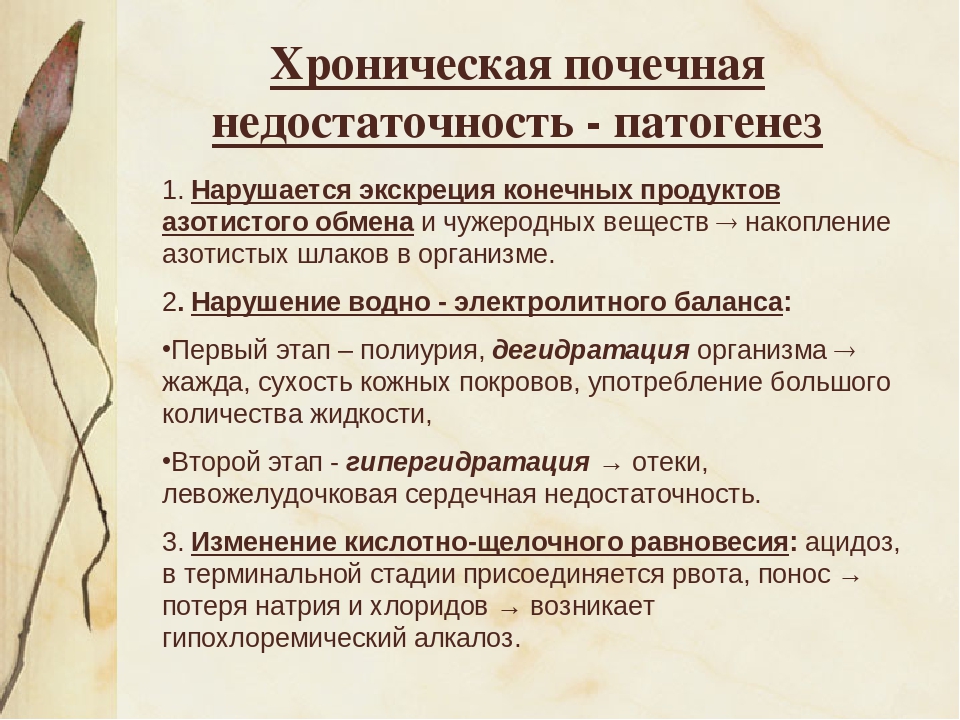

Причинами почечной недостаточности могут быть различные заболевания, травмы или генетические факторы.

Симптомы почечной недостаточности могут включать отеки, повышенное давление и изменение цвета мочи.

Степень выживаемости без почек зависит от индивидуальных характеристик организма и вида почечной недостаточности.